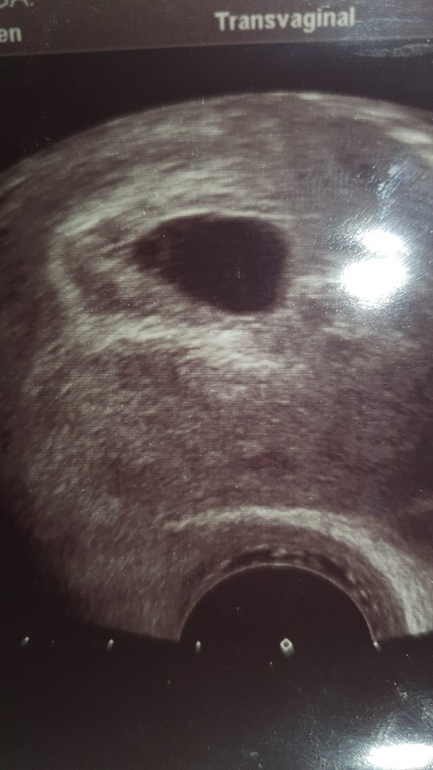

Лёся

Подруга попросила узнать, поскольку тут знающие люди есть: узи на 5+6

Посмотрите, пожалуйста))

Контуров хориона. Он ведь на узи виден как более светлая область вокруг плодного яйца, верно?

Ого, не думала, что хорион такой большой. А это нормально, что контуров не видно?